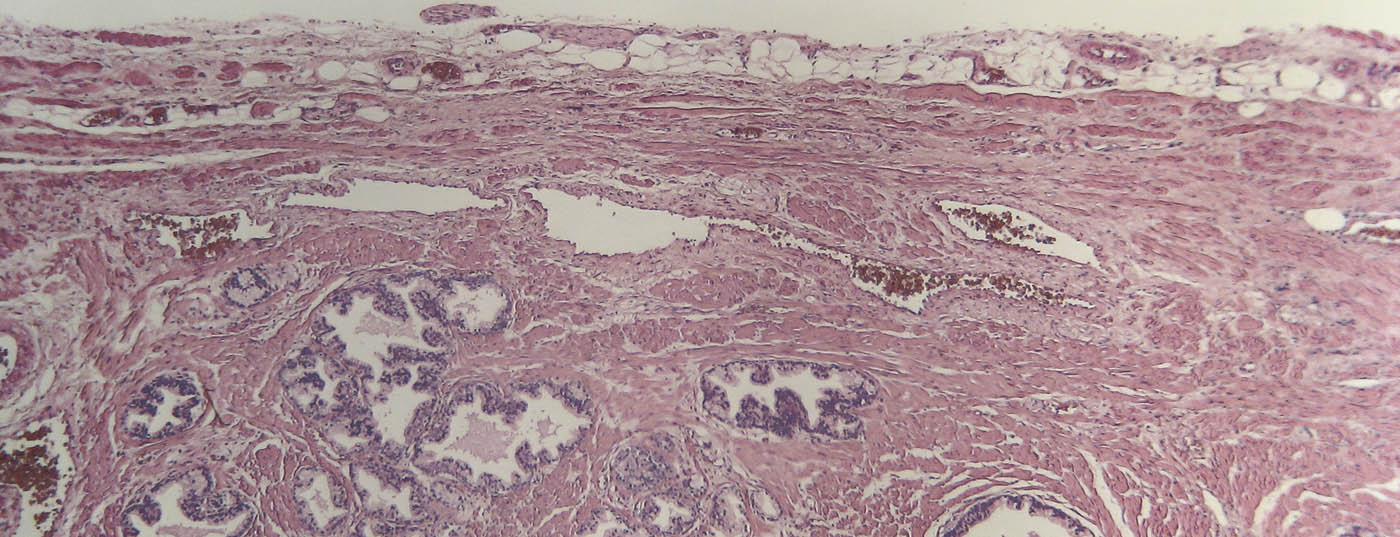

prostata_histo

• Diagnostik und Therapie beim fortgeschrittenen Prostatakarzinom

Stand der Evidenz

Bei klinisch lokal fortgeschrittenem Prostatakarzinom kommen radikale Prostatektomie und externe Radiotherapie in Frage. Beim metastasierten Prostatakarzinom sind ADT, ADT plus Docetaxel sowie ADT plus Abirateron und Prednison denkbar.